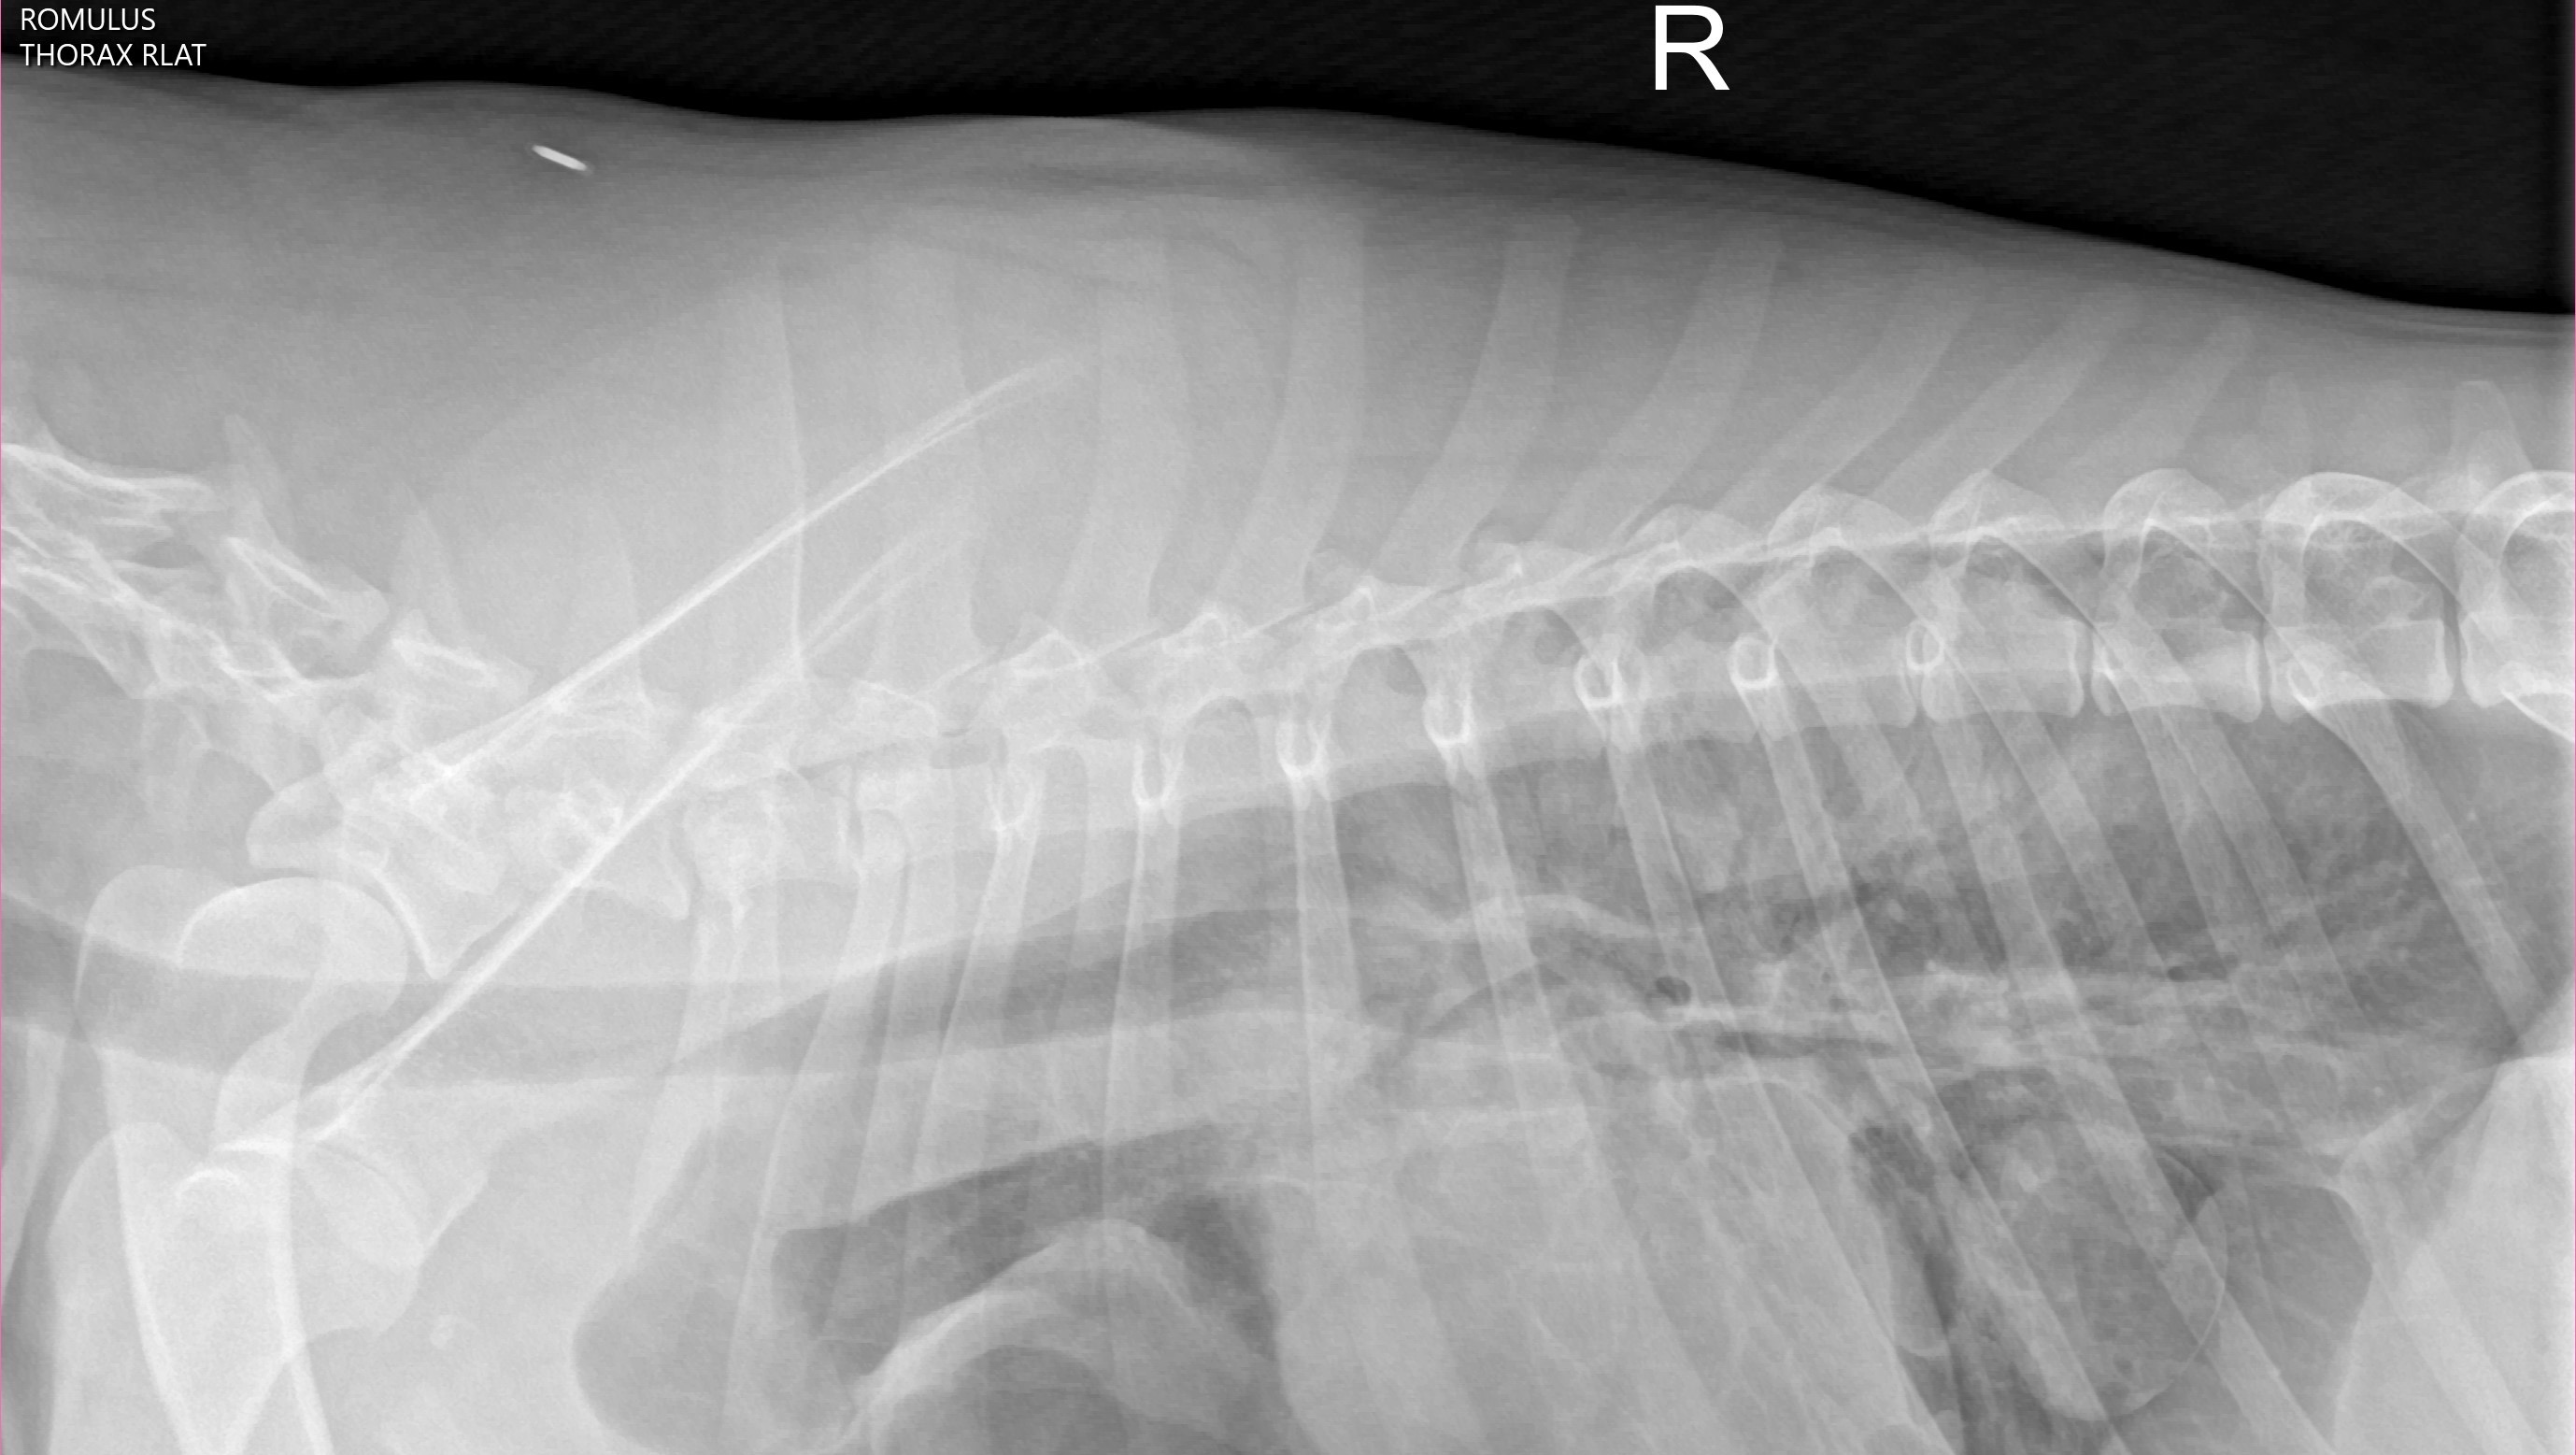

Although our hearts are over joyed to have our boy back, we just received terrible news. It looks like Romulus may have been hit by a car on his adventure away from home and needs emergency surgery to repair a diaphragmatic hernia. We are on our way to UC Davis as we speak to have a consult with a surgeon who has quoted roughly 3-5k for the initial visit and stabilization with another 10-15k for the actually surgery itself. Thankfully Romulus does have insurance, however, they will not cover the entire cost so we are asking for a little bit of help from whoever is willing and able to assist us with our baby boys veterinary bills.